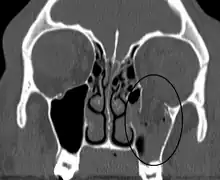

| An orbital blowout fracture of the floor of the left orbit. | |

An orbital blowout fracture is a traumatic deformity of the orbital floor or medial wall that typically results from the impact of a blunt object larger than the orbital aperture, or eye socket.[1] Most commonly this results in a herniation of orbital contents through the orbital fractures.[1] The proximity of maxillary and ethmoidal sinus increases the susceptibility of the floor and medial wall for the orbital blowout fracture in these anatomical sites.[2] Most commonly, the inferior orbital wall, or the floor, is likely to collapse, because the bones of the roof and lateral walls are robust.[2] Although the bone forming the medial wall is the thinnest, it is buttressed by the bone separating the ethmoidal air cells.[2] The comparatively thin bone of the floor of the orbit and roof of the maxillary sinus has no support and so the inferior wall collapses mostly. Therefore, medial wall blowout fractures are the second-most common, and superior wall, or roof and lateral wall, blowout fractures are uncommon and rare, respectively. They are characterized by double vision, sunken ocular globes, and loss of sensation of the cheek and upper gums from infraorbital nerve injury.[3]

Thin cut (2-3mm) CT scan with axial and coronal view is the optimal study of choice for orbital fractures.[16][17]

Plain radiographs, on the other hand, do not have the sensitively capture blowout fractures.[18] On Water's view radiograph, polypoid mass can be observed hanging from the floor into the maxillary antrum, classically known as teardrop sign, as it usually is in shape of a teardrop. This polypoid mass consists of herniated orbital contents, periorbital fat and inferior rectus muscle. The affected sinus is partially opacified on radiograph. Air-fluid level in maxillary sinus may sometimes be seen due to presence of blood. Lucency in orbits (on a radiograph) usually indicate orbital emphysema.[4]